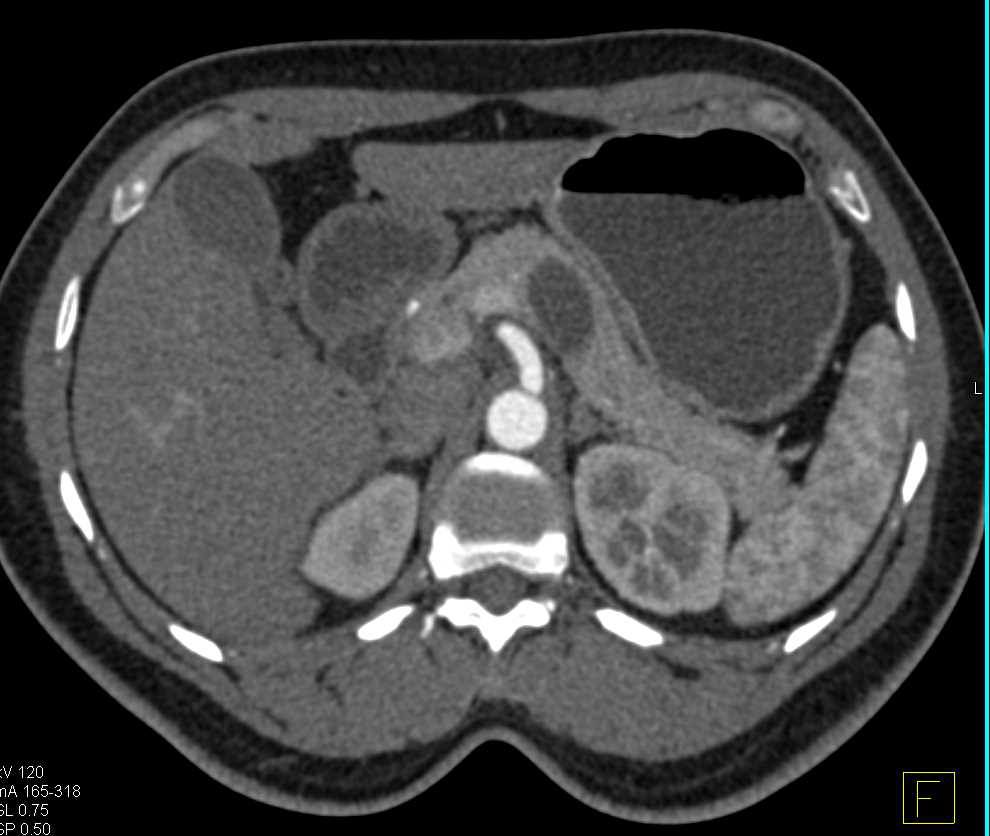

Subtle Carcinoma Head of Pancreas with Dilated Pancreatic Duct